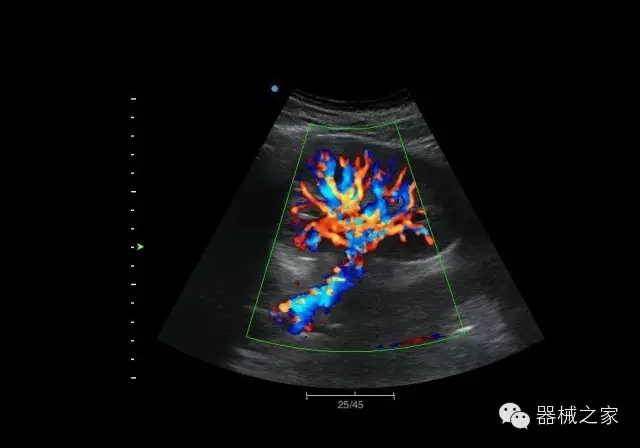

臨床圖片賞析

腎臟血流

肝血管瘤